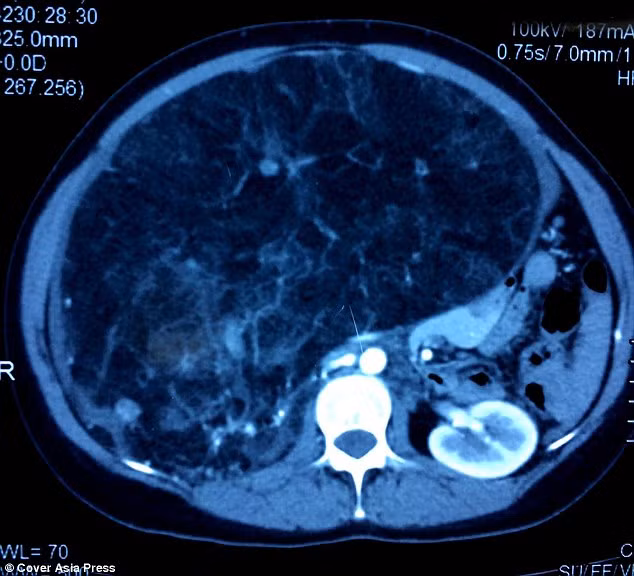

| Ảnh chụp X-quang cho thấy khối u đè lên thận. |

Kết quả cho thấy bệnh nhân này bị một khối bướu mô liên kết lành mọc dính vào thận khiến thận không hoạt động được rồi bị suy. Hơn nữa vì kích thước và vị trí của khối u khá nguy hiểm vì chỉ cần một tổn thương nhỏ ở vùng bụng cũng có thể dẫn đến chảy máu trong và có thể khiến bệnh nhân mất mạng.